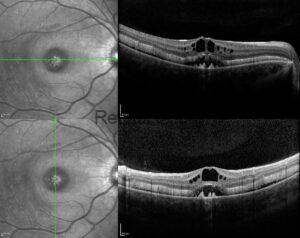

X-linked Retinoschisis

A 17-year-old male with a history of vitreoretinal surgery presented to the retina department for [...]